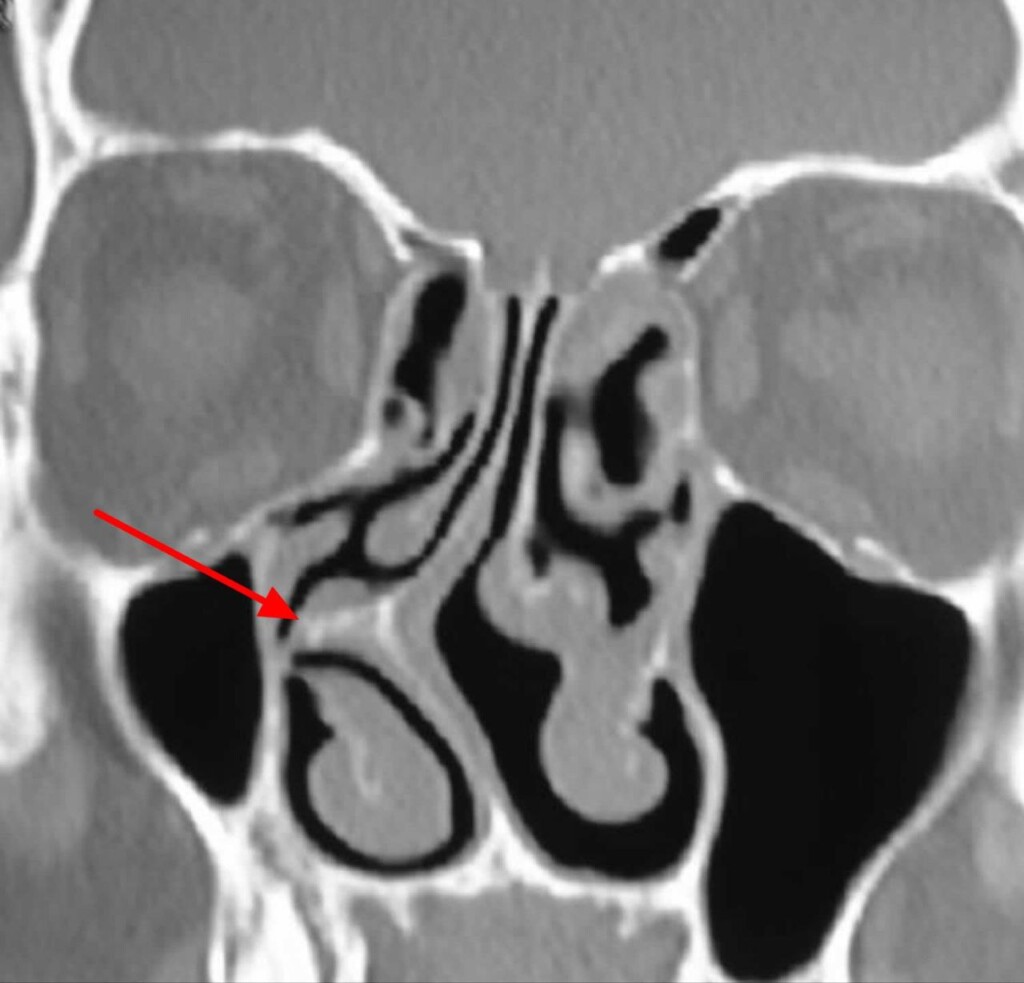

Под рентгеном

1. Подготовка – консультация ЛОР-врача, КТ или рентген околоносовых пазух, анализы крови.